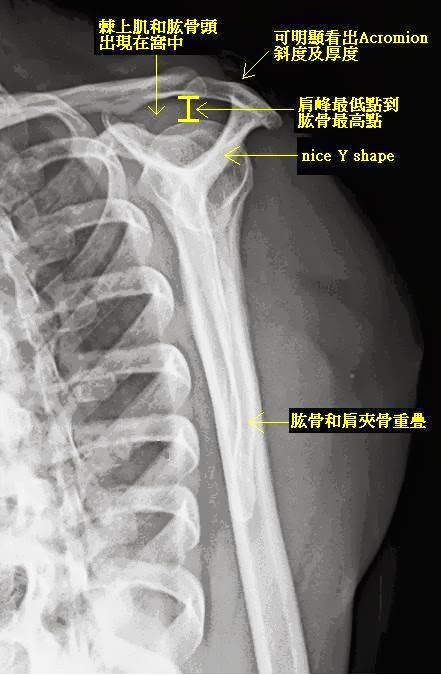

A1. 照得好、標準的X光棘上肌出口投射照* (Supraspinatus Outlet View圖1.)可以看出肩

峰下的乾坤。

估計,只要拱門標高低 (“矮”)了2mm,就會五十肩,肩峰減壓成形術就是以這數據來作指引。

*關於棘上肌出口投射照,歡迎網訪 http://docwglee.blogspot.tw/2011/09/x.html or http://classic-blog.udn.com/wglee/5639719